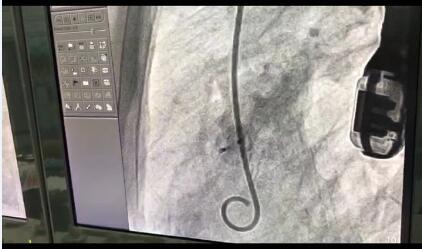

(Dr.Pimpak Prachasilchai使用KONAR-MF?多职能封堵器进行封堵手术)

(术后造影)